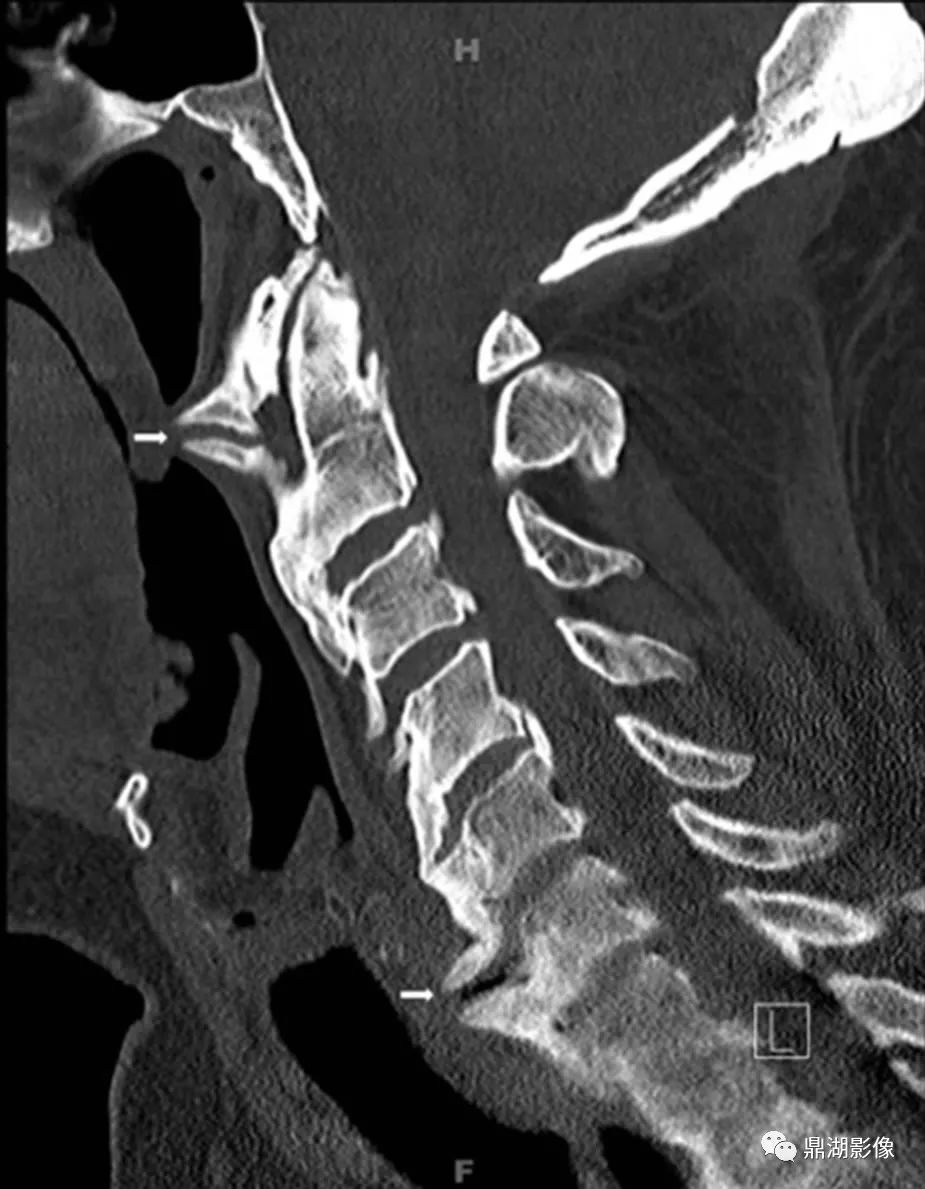

- 椎体前外侧连续性骨化,后纵韧带、黄韧带也可受累非边缘性韧带骨赘,即骨化不发生于间盘边缘,形成波浪样外观

- 随时间进展骨化厚度可从1-2mm增至20mm

- 椎间隙高度正常